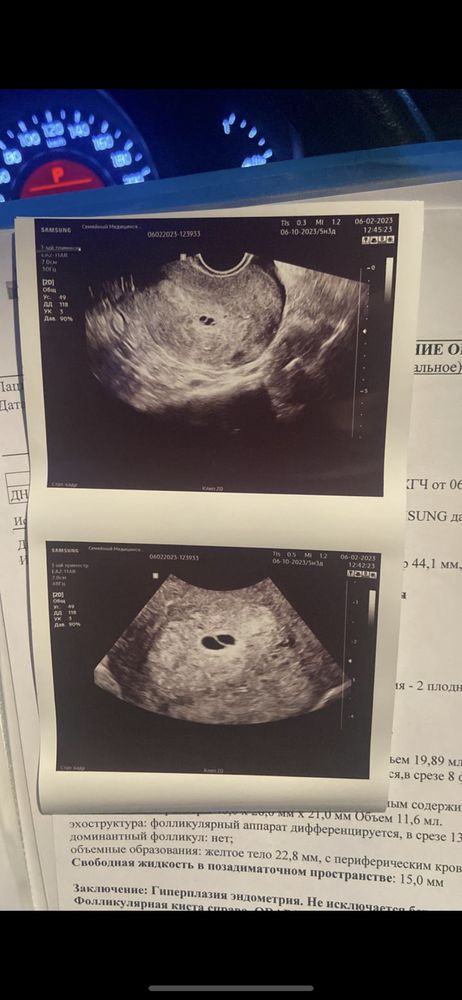

Была ли беременность подскажите, пожалуйста! Врач пишет «не исключается беременность»

Так пишут, потому что эмбриона не видно. Либо пока , потому как срок не понятен. И вообще я бы сказала что похоже на монохориальную двойню, там как бы два пузырика, но оба без эмбриона. Может, еще рано?

Ксения , сама врач тоже не исключала двойню,но так как непроходимые трубы отправили на гистероскопию,а теперь я думаю,а была ли беременность?

Виктория, а потом вы в динамике сдавали? Вообще при таком ХГЧ на УЗИ толком то ничего и не видно.